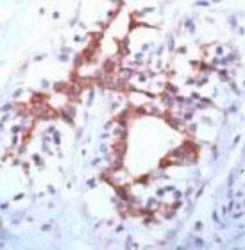

Supportive validation

- Submitted by

- Abnova Corporation (provider)

- Main image

- Experimental details

- Immunohistochemical staining of FGFR3 on formalin fixed, paraffin embedded human breast cancer with FGFR3 polyclonal antibody (Cat # PAB11649).

- Validation comment

- Immunohistochemistry (Formalin/PFA-fixed paraffin-embedded sections)